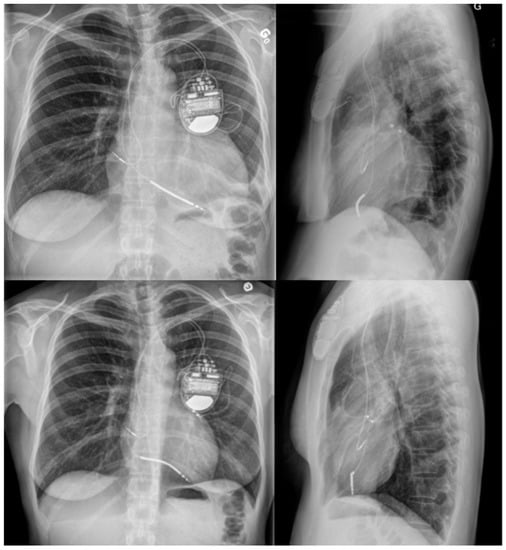

2. Case Report